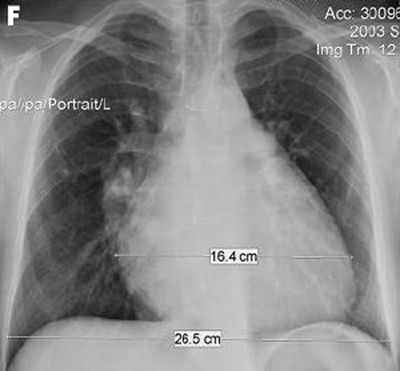

Ressonância nuclear magnética em um paciente com regurgitação pulmonar após reparo de tetralogia de Fallot. O paciente tem ventrículo direito não restritivo e o coração é grande

De: Chaturvedi RR, Redington AN. Heart. 2007 Jul;93(7):880-9; usado com permissão